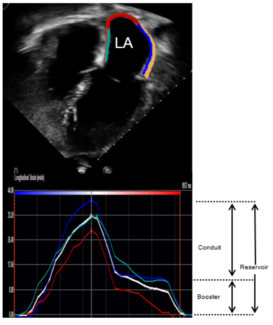

Omar Abozied, MD; Dhanya Ramachandran, MD; Alexander C. Egbe, MBBS, MPH, MD, MS; William R. Miranda, MD; Jason H. Anderson, MD; Heidi M. Connolly, MD; Jae K. Oh, MD; Kartik Andi, MD; Ahmed Goda, MD

The purpose of this study was to determine whether LA strain cut-off points can detect increased LV filling pressure in adults with coarctation of aorta.